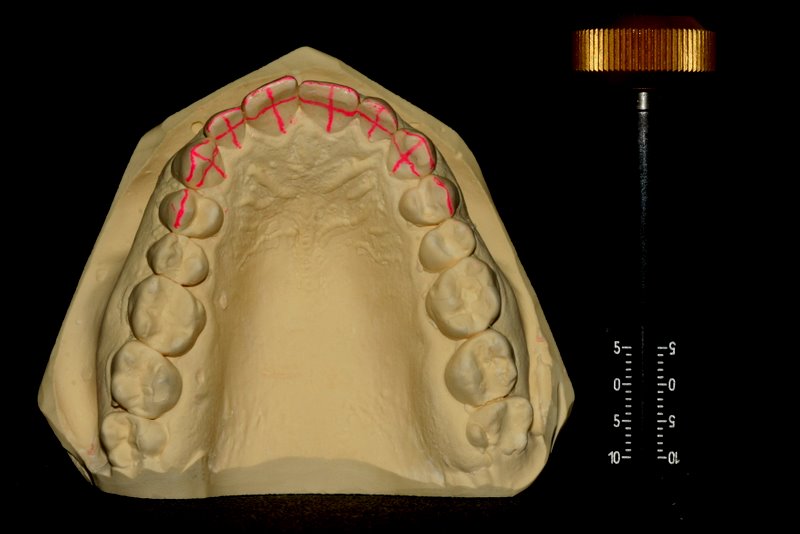

Invisalign, das hat sich die Firma lange Zeit gut bezahlen lassen, durch die erfolgreiche Therapiekonzepte drängten immer mehr Anbieter auf den Markt und heute ist man als Patienten in der Lage zwischen vielen möglichen Anbietern zu wählen. Wir arbeiten mit Invisalign, machen uns aber Schienen auch selber, denn das nötige Equipment wie 3D Drucker und entsprechende Software haben wir im Haus.